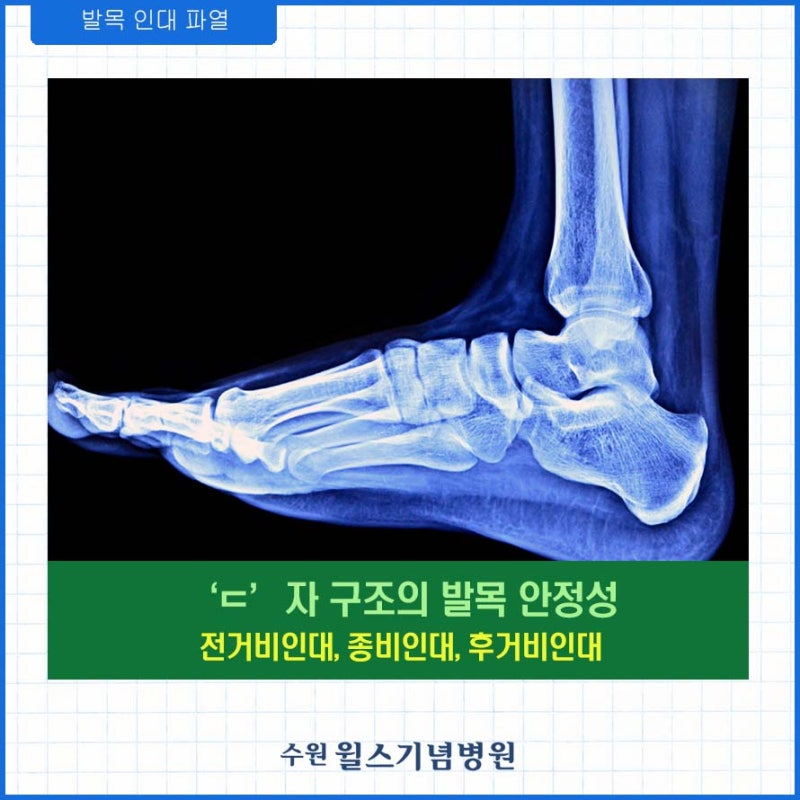

발목을 부러뜨릴 때 대부분 발목이 안쪽으로 휘어지는 내분 현상을 경험합니다. 이때 발목 바깥쪽 부분에서 손상이 생깁니다. 대개 뼈와 뼈를 연결해 관절의 안정성을 뒷받침하는 조직적인 인대 손상을 입는 경우가 많습니다. 처음부터 심하게 다쳐서 발목 인대 파열이 크게 진행되는 경우도 있지만 발목 염좌의 80% 이상은 인대 손상이 크지 않은 편입니다.주변 근육이 갑작스러운 충격에 놀라 수축하게 되면 통증이 느껴지는 경미한 염좌에서 인대가 조금 늘어난 1도 염좌, 인대 손상과 함께 발목 불안정성을 동반한 2도 염좌, 발목 인대가 완전히 파열되면 발목 안정성이 상실된 3도 염좌로 구분될 수 있습니다. 발목 관절의 안정성을 뒷받침하는 발목 인대 파열이 심할수록 발목은 약해집니다.